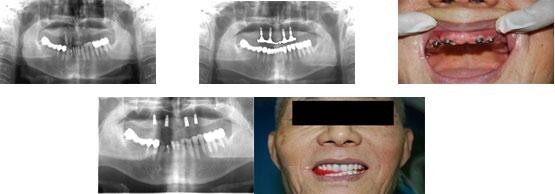

style="text-align: center;"> 种植牙修复前后效果图,更多详情sp>an>a